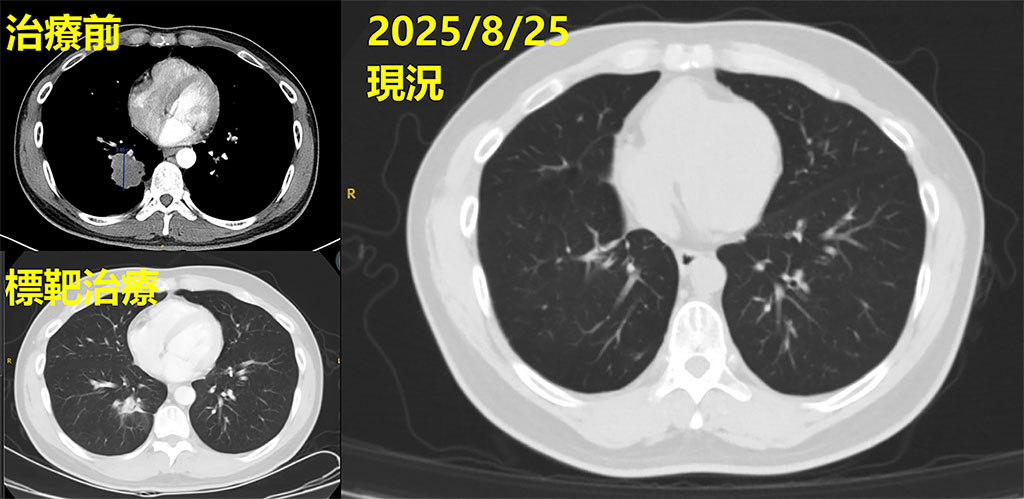

「病人剛入院時,我們先依臨床流程完成初步的基因檢測,但結果未發現可使用的突變標靶。」林聖皓主任說明,後續團隊持續評估治療方向,並協助病人參與國家衛生研究院的臨床基因試驗,最終發現具EGFR exon 19 deletion突變,得以申請第三代EGFR標靶藥物,使治療更具針對性與精準性。經過一段時間,影像追蹤顯示肺部腫瘤從原本的4公分縮小為2.8公分,控制成效顯著。

經治療後影像追蹤可見,原近4公分腫瘤明顯消失,病情獲得良好控制。